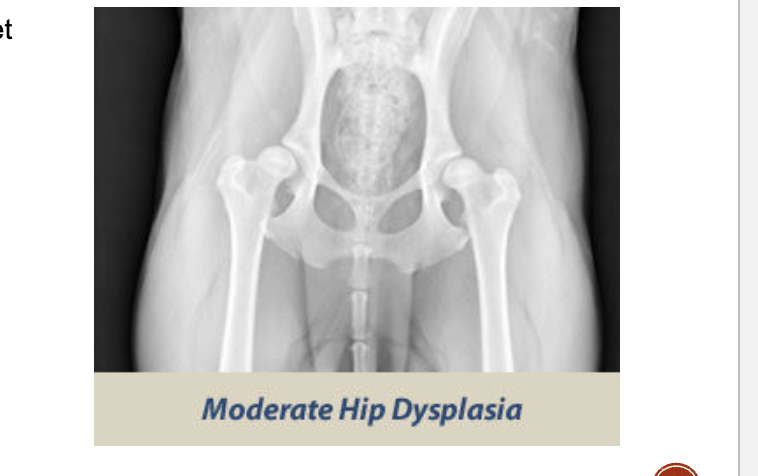

OFA moderate dysplasia

Ball is barely seated in the shaloow socket

Secondaary arthritic bone changes